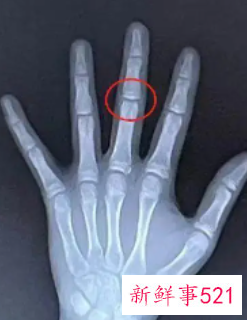

骨龄偏大可以降下来,对手、腕、髋和膝等大关节的骨骺以及骨骺线,可以通过X光片进行观测,了解骨骺及骨骺线的闭合与出现情况,以此来观测骨龄。那么骨龄偏大可以降下来吗?

骨龄偏大是指骨龄的测试比实际年龄要大,一般骨龄与实际年龄之间是有一定差别的。正常在1-3岁以内是正常范围,如果>2岁就提示有骨龄大于实际年龄,一般是性早熟。

骨龄偏大一般不可以降下来。骨龄偏大是指经测试发现骨的年龄要大于正常的年龄,一般是由于过度肥胖、食用较多激素类食物等因素引起。如果骨骺线已经闭合,则无法再使骨龄下降。

但是,如果骨骺线刚刚开始闭合,则可以通过减重、改善饮食、运动等方式促使骨骺线闭合延迟,从而使身高再次生长。骨龄偏大的孩子多数存在性早熟的现象,所以家长需时刻观察孩子的情况。

儿童骨龄偏大意味着什么

孩子骨龄偏大,也就意味着孩子骨龄提前,超越年龄,而骨龄偏大则骨骺线闭合的时间也会比较早,就意味着孩子生长发育的时间和空间都缩小了。而孩子的骨骺线一旦完全闭合,也就意味着孩子的身高将终止增长。

儿童的骨龄与实际年龄偏差1岁以内属正常,如果孩子没有疾病,只是骨龄偏大,可以通过调整饮食、运动和睡眠帮助孩子恢复到正常骨龄,让孩子达到理想身高。如果骨龄大大超过实际年龄,则可能是性早熟、肾上腺疾病等引起,应请医生对症治疗。